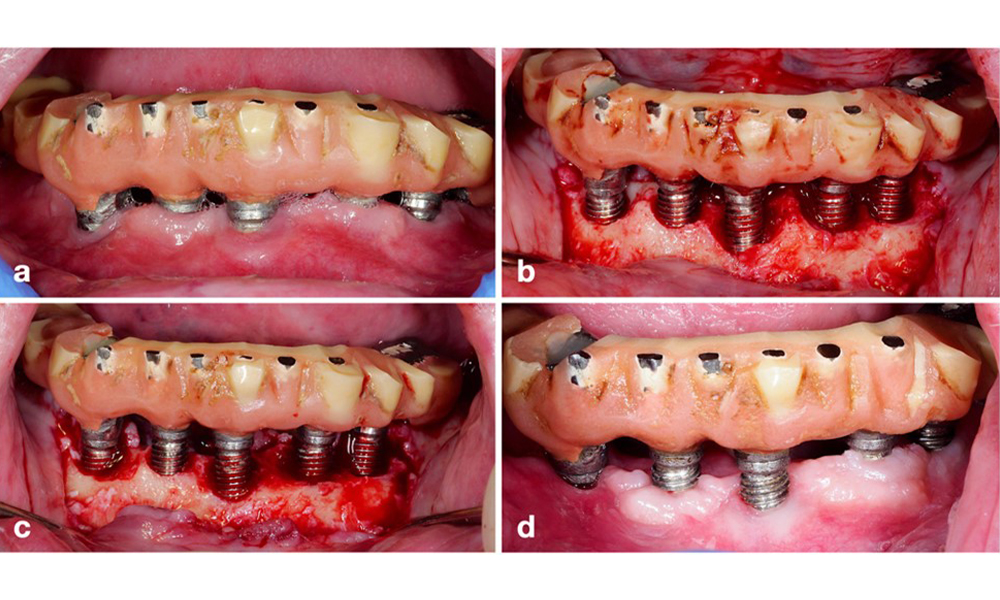

Defect extent, implant position, and its strategic importance determine whether an implant can or should be treated. Similar to a non-treatable (hopeless) implant, a severely affected implant in a multiple-unit restoration may be irrelevant for treatment, as its loss does not compromise the prosthetic restoration. Consequently, it is advisable to consider explantation either upon diagnosis or during surgical intervention (figure 8).

Explantation of a severely affected implant using a piezo surgery device. The implant in position 43 was part of a 4-unit bridge supported by 3 implants. Because of significant bone loss and minor relevance in the support for the bridge, treating the implant was deemed impractical. Explantation was performed with a piezo surgery device and specially designed tips (a-c) ensuring a minimal amount of bone loss (d).

Figure 8. Explantation of a severely affected implant using a piezo surgery device. The implant in position 43 was part of a 4-unit bridge supported by 3 implants. Because of significant bone loss and minor relevance in the support for the bridge, treating the implant was deemed impractical. Explantation was performed with a piezo surgery device and specially designed tips (a-c) ensuring a minimal amount of bone loss (d).